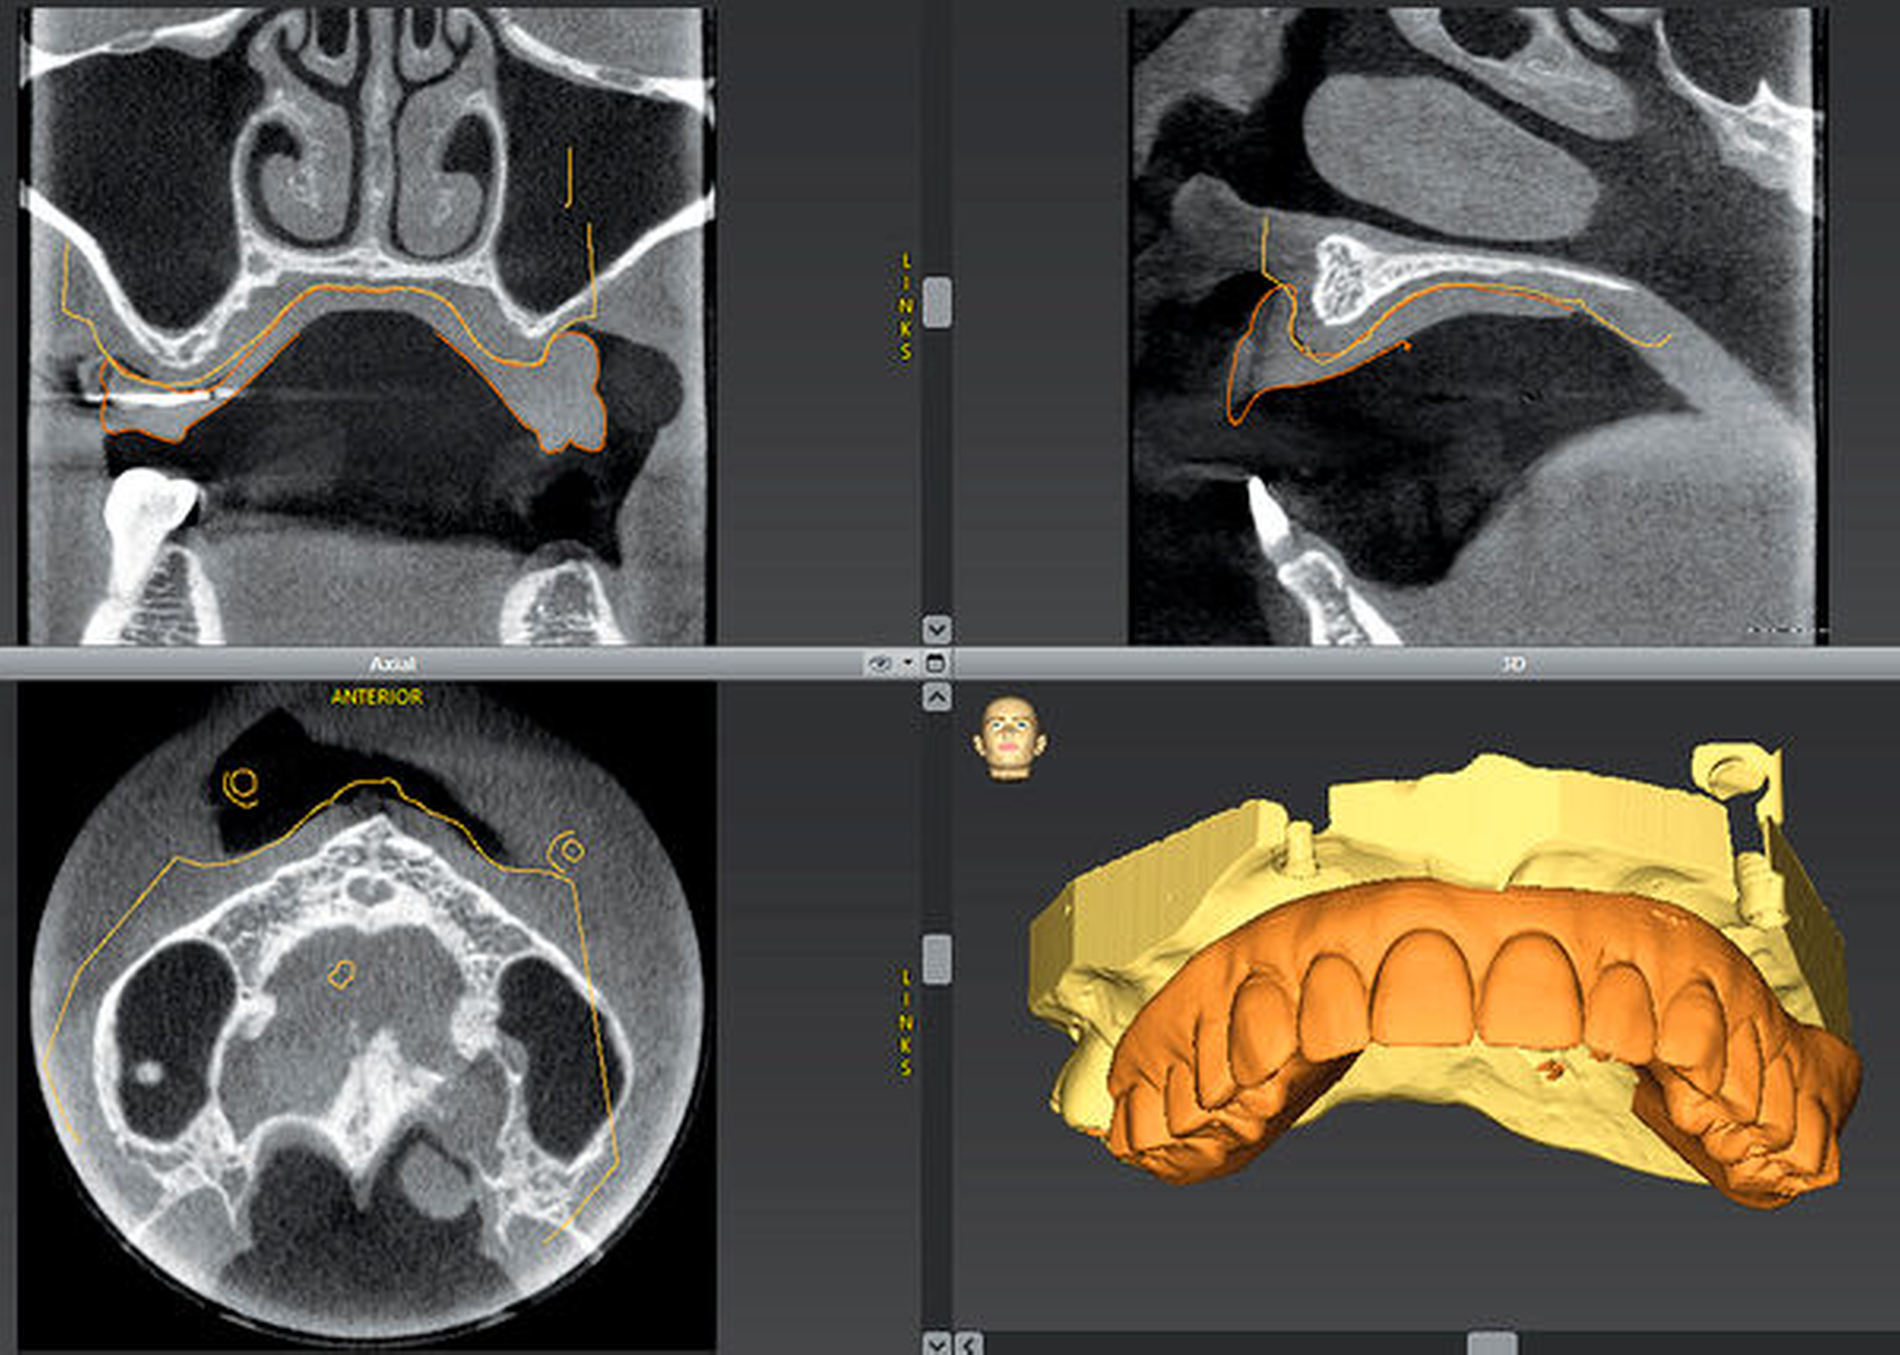

Nachteilig bei all diesen Verfahren und damit letztlich ein deutlicher Hinderungsgrund für die Einführung in der Praxis war die Notwendigkeit, vor der DVT-Aufnahme eine spezielle radiologische Schablone herzustellen oder eine vorhandene Prothese zu modifizieren. Mit der Einführung intraoraler Scanner oder auch der Möglichkeit, Modelle nachträglich zu scannen, besteht bei aktuellen Planungssystemen nun die Möglichkeit, den gescannten Datensatz mit dem radiologischen Datensatz anhand von charakteristischen Bildpunkten (Zahngeometrie) zu matchen. Dieses Verfahren wird in der Literatur teilweise als „Smart Scan“ oder „Smart Fusion“ beschrieben [Vico et al., 2016].

Soll eine OP-Schablone digital designt werden, muss zunächst ein Oberflächendatensatz der teil- oder unbezahnten Situation gematcht werden. Da auf dieser Oberfläche die Schablone gestaltet wird, mit der die Übertragung der virtuellen Planung erfolgt, ist es an dieser Stelle besonders wichtig, dass das Matchen hochpräzise möglich ist. Sehr unterschiedlich und zum Teil schwierig kann die Umsetzung bei einer geplanten Sofortimplantation sein. Wenn an der zukünftigen Implantatposition noch Zähne vorhanden sind, die erst intraoperativ entfernt werden, kann die optimale Positionierung der Bohrhülsen oft schwierig sein. Selbstverständlich lässt sich auch der Scan einer späteren prothetischen Versorgung mit den radiologischen Bilddaten matchen, um so die Implantatposition und die Implantatachse bestmöglich auf die angestrebte Versorgung auszurichten. Mit dieser deutlich alltagstauglicheren Methode wird aus der reinen Knochendarstellung des DVTs tatsächlich eine echte bidirektionale Visualisierung auch der prothetischen Versorgung.

Im teilbezahnten Gebiss lassen sich mit der Verschmelzung der Oberflächendaten aus den intraoralen Scannern oder den gescannten Modellen sowie der radiologischen Daten extrem einfach und chairside sinnvolle Planungen und Visualisierungen erstellen. Der Informationsgewinn gegenüber der rein radiologischen Darstellung ist sicherlich immens. Kritisch ist allerdings zu bedenken, dass dieses Verschmelzen abhängig davon ist, dass die Bilddaten in entsprechender Weise aufgenommen wurden. So sollte der Patient möglichst seine Zähne nicht in Okklusion halten, da sonst eine Identifikation der Zahnoberflächen während der Segmentierung schwerer gelingt. Dies ist auch beim Vorliegen vieler Metallartefakte der Fall. Die Segmentierung, also die Darstellung der radiologischen Zahnoberflächen ist dann häufig nur sehr ungenau. Dies erschwert ein präzises Matchen oder macht dies unmöglich – so wie es auch im teilbezahnten Gebiss mit stark reduzierter Restbezahnung der Fall sein kann. Gelingt ein automatisiertes Matchen nicht, kann dies in der Regel „händisch“ durch Feinjustierung versucht werden. Dies führt jedoch bei stark reduzierter Restbezahnung (je nach Verteilung der Restzähne) oder bei vielen Metallartefakten auch mit einiger Erfahrung oft nicht zu befriedigenden Ergebnissen. Diese möglichen Ungenauigkeiten werden in der wissenschaftlichen Diskussion zurzeit wohl leider etwas unterschätzt [Wismejier et al., 2018].